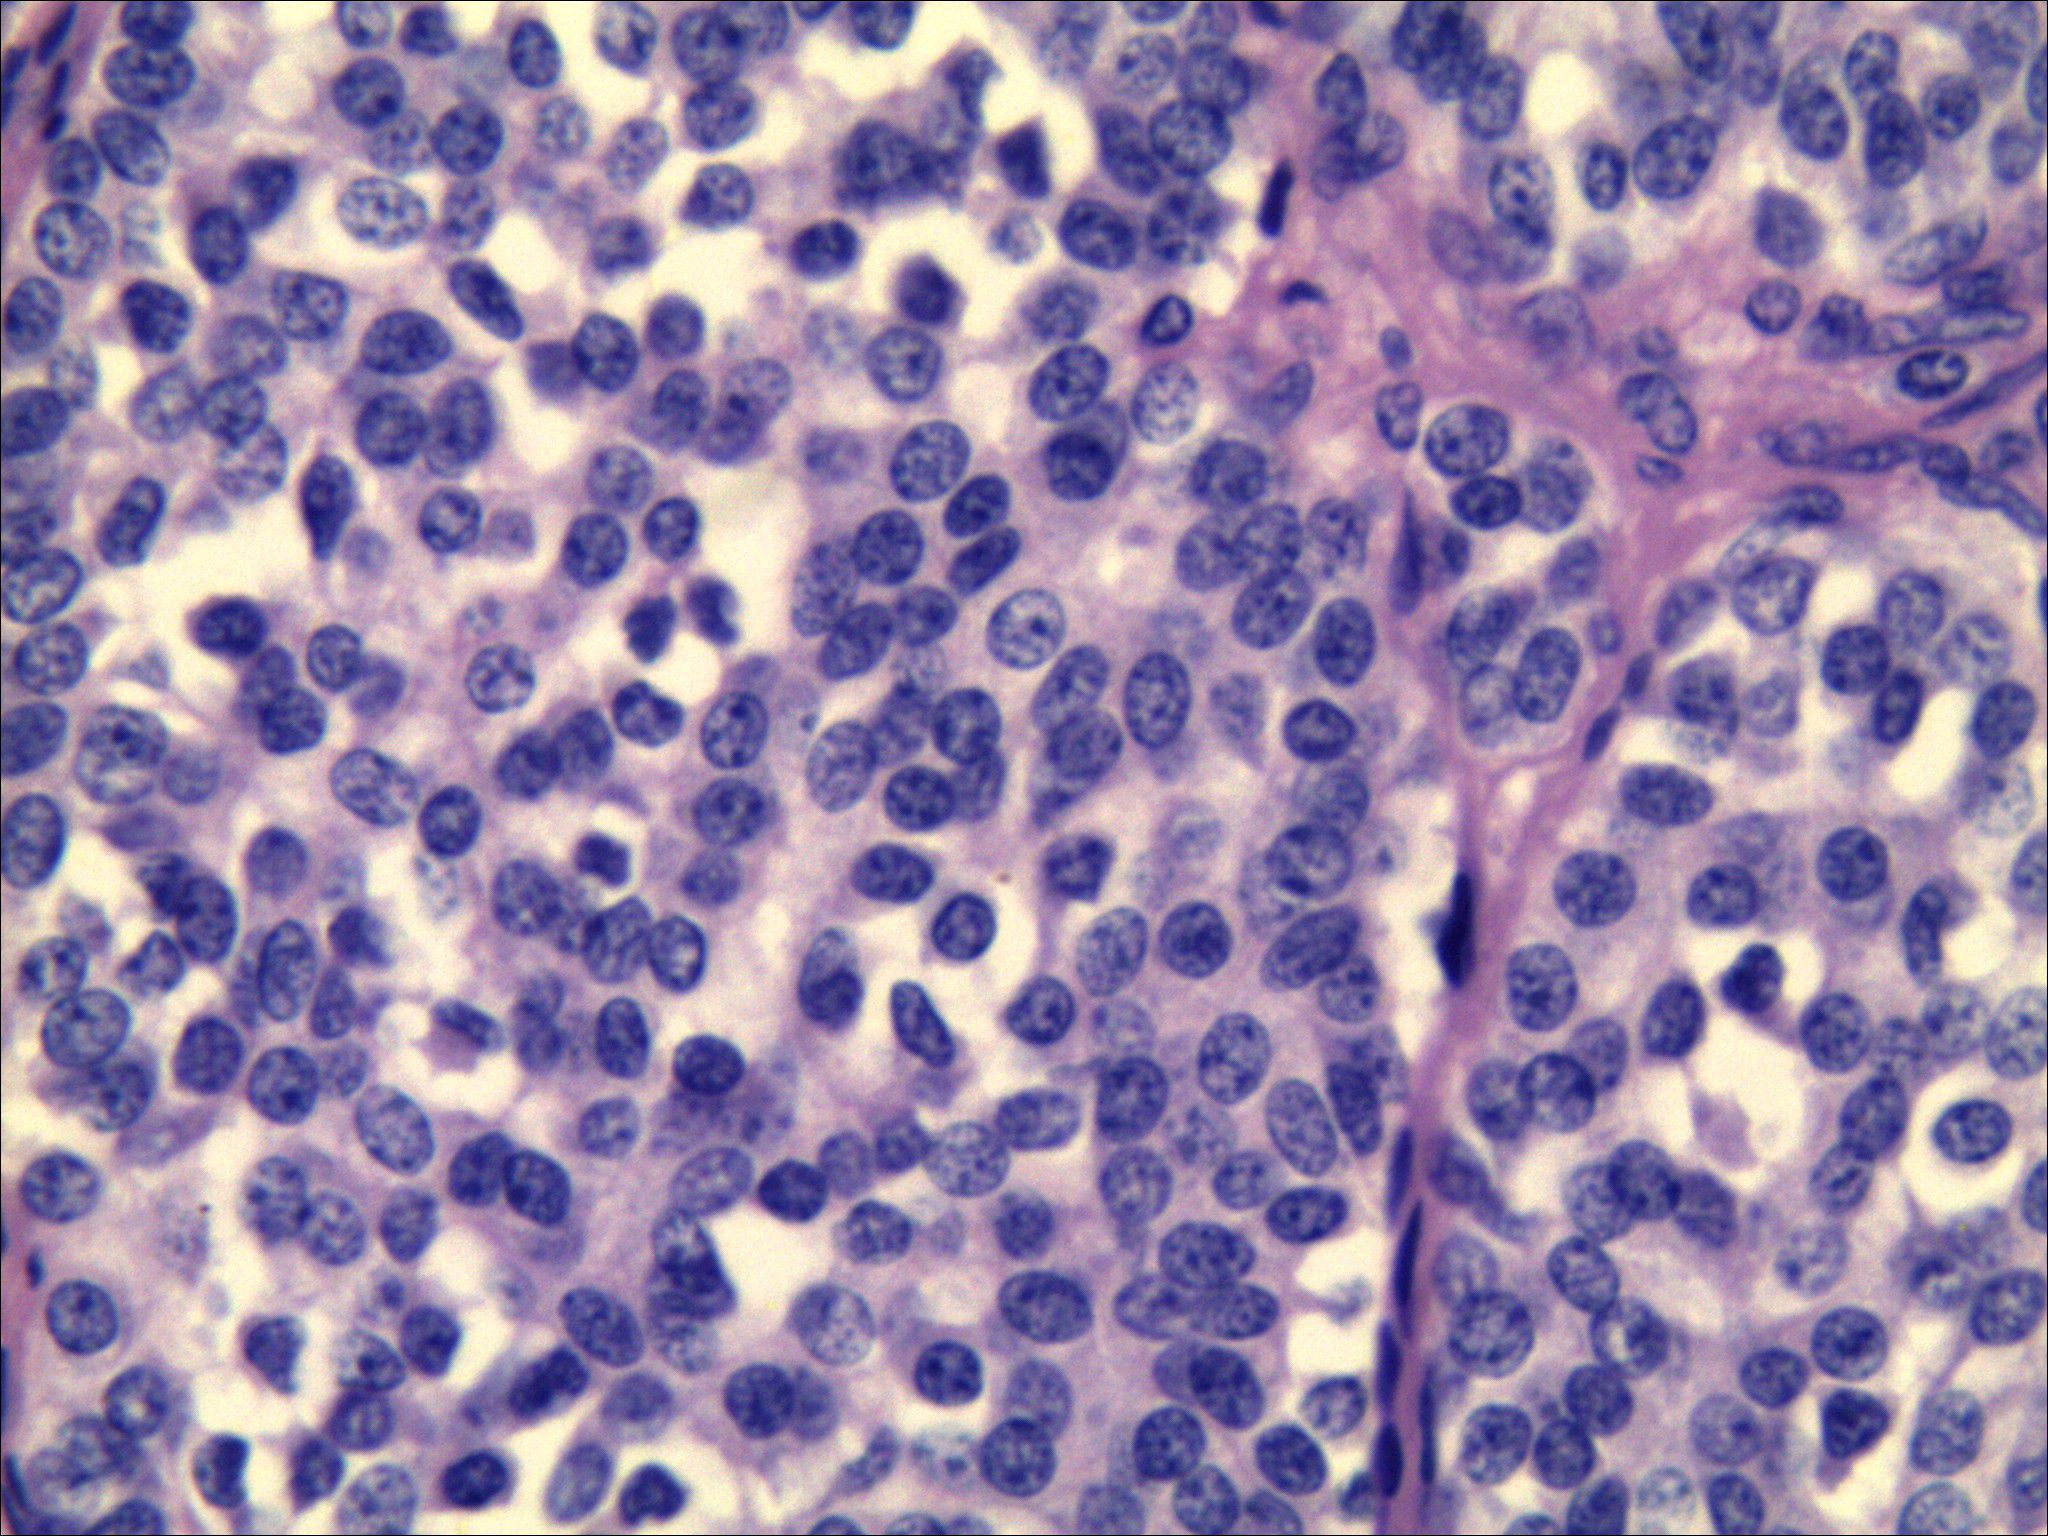

The tumor cells displayed round, polygonal, or plump spindle morphology containing moderate amphophilic cytoplasm, with round-to-oval nuclei showing salt-and-pepper chromatin and rare mitoses. Immunohistochemical analysis confirmed CT (+), Carcinoembryonic antigen (CEA) (+), Syn (+), CgA(+), TTF-1(+), Ki-67(10%), and CK (+) expression, while special stains revealed Congo red (methanol method) (+) and acid-fast red (+) reactivity. These morphological and immunohistochemical findings collectively confirmed medullary thyroid carcinoma (Figure 5), with the largest tumor focus measuring 0.2 cm without capsular invasion; adjacent thyroid tissue exhibited nodular goiter.

Figure 5

Microscopic view of densely packed, purple-stained cells with various shapes and sizes. The cells have prominent nuclei and are separated by thin, connective tissue strands.

Figure 5. Pathological results after surgical resection of thyroid nodules. Morphology combined with immunohistochemistry confirmed medullary thyroid carcinoma. [HE staining ×400, CT (+), CEA (+), Syn (+), CgA (+), TTF-1 (+), Ki-67 (10%), CK (+)].